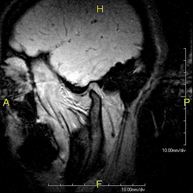

- Brain MRI (cranial)

This non-invasive diagnostic procedure uses an electromagnetic field and radio waves (from a transmitter and receiver) to acquire high-definition anatomical images of the brain. It is a radiation-free procedure. Indicated for: vascular problems, memory loss, epilepsy, headache, malformations, suspected tumour, meningitis.